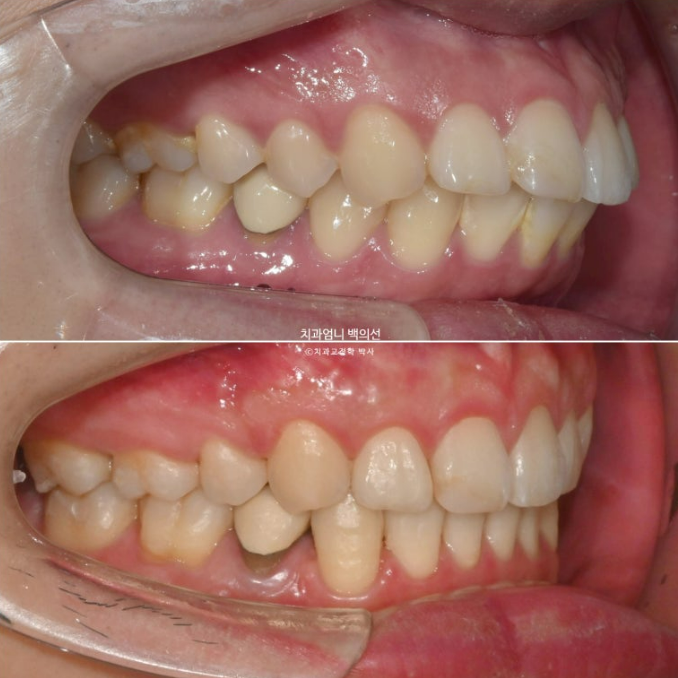

2024년 6월부터 11월까지, 20개의 추가장치를 모두 낀 후 모습입니다.

24.11

앞니 사이 틈은 없어졌고 중심선은 정확히 맞습니다.

교합도 퍼펙트 합니다.

입안 사진만 보면 치료를 마무리해도 됩니다.

24년 12월부터 25년 4월까지, 16개의 두번째 추가장치를 모두 낀 후 모습입니다.

25.05

교합이 좋지 않으면 치료를 마무리 짓지 않습니다.

이제 전후 비교 보겠습니다.

총 치료기간은 2년 6개월이며 재제작은 총 2회 했습니다.